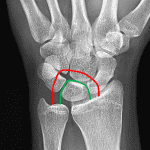

- Acute perilunate dislocation

- Acute scaphoid waist fracture with 5 mm radial displacement of the distal fracture fragment

- Osseous fragments along the dorsal margin of the distal radius

- Perilunate dislocation

Acute transscaphoid perilunate dislocation with 5 mm radial displacement of the distal scaphoid waist fracture fragment.

Osseous fragments along the dorsal margin of the distal radius may represent shear fractures from Lister’s tubercle or from the dorsal lunate.